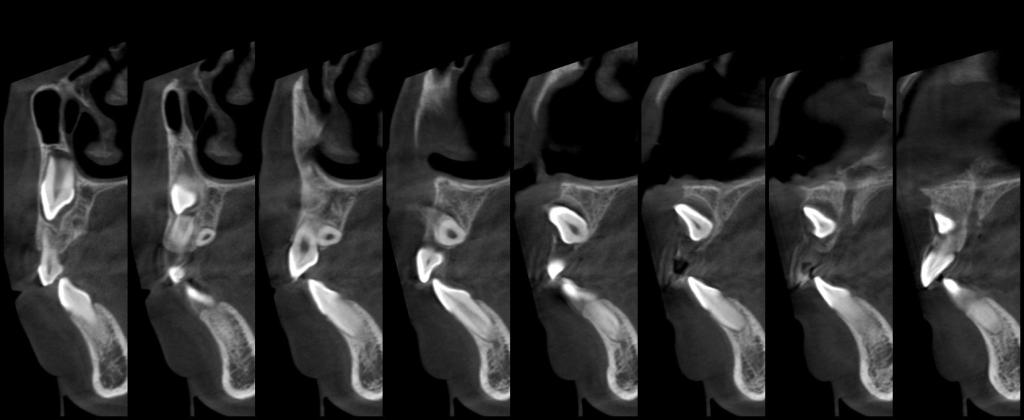

颅颌面CBCT

诊断范围涉及牙体牙髓病、牙周病、阻生牙/多生牙定位、种植牙术前CT评估分析、颞下颌关节CT诊断分析、,颌骨及涎腺疾病、颌面发育畸形、正畸治疗辅助诊断等大部分颌面部疾病,为临床医疗提供强有力的支持。